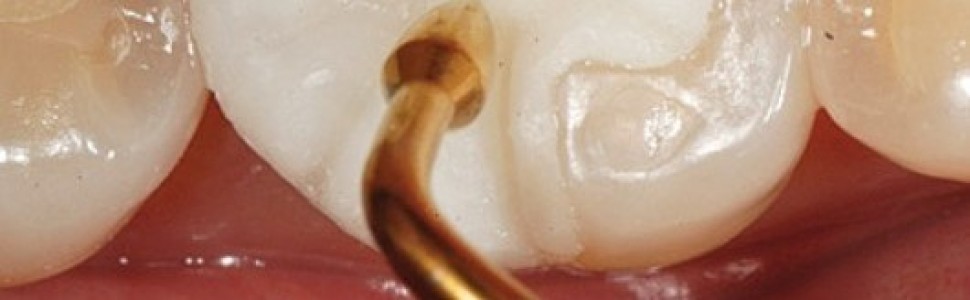

Immediate dentin sealing (IDS) – natychmiastowa aplikacja systemu łączącego na zębinę, dawniej „technika podwójnego wiązania”

Aplikacja systemu wiążącego na świeżo ściętą zębinę po opracowaniu zębów, tzw. natychmiastowe uszczelnienie zębiny (immediate dentin sealing – IDS), zostało zaproponowane jako alternatywa dla opóźnionego uszczelnienia zębiny (delayed dentin sealing – DDS), techniki w której żywice adhezyjną nakłada się tuż przed ostatecznym połączeniem adhezyjnych uzupełnień pośrednich (indirect adhesive restorations – IAR). Minimalnie inwazyjne procedury protetyczne (minimally invasive prosthetic procedures – MIPP), rozwój materiałoznawstwa, niezawodnych technik adhezyjnych oraz coraz większe zapotrzebowanie na uzupełnienia estetyczne, tj. licówki ceramiczne, wkłady, nakłady i korony pełnoceramiczne spowodowały zwiększony nacisk na zachowanie zdrowej struktury zęba. W pracy opisano technikę IDS, zwracając uwagę na jej minimalnie inwazyjny charakter oraz zalety, zwłaszcza w porównaniu z DDS.